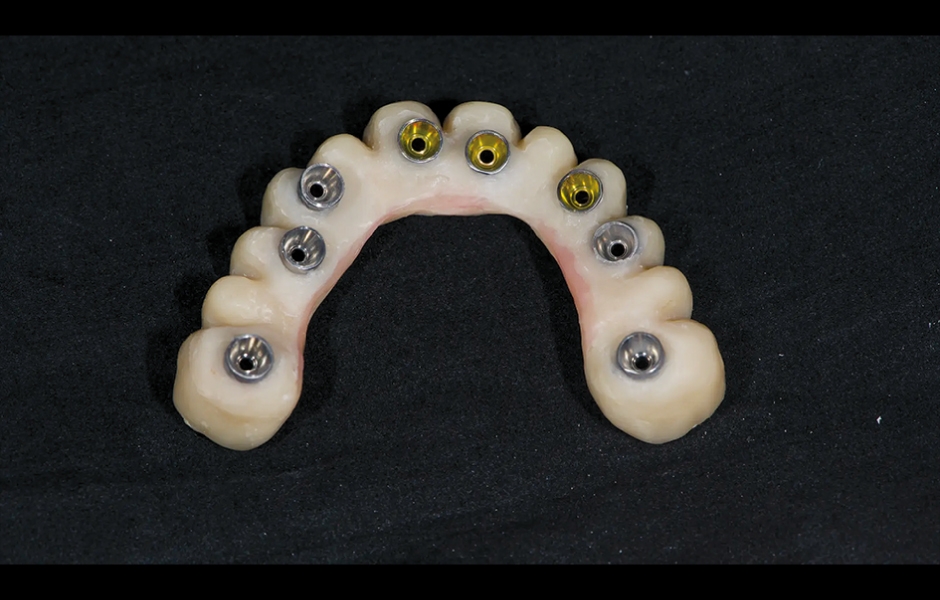

Při finální návštěvě byla nasazena definitivní hybridní šroubem fixovaná protetika. Definitivní práce sestávala z CAD/CAM titanového skeletu přišroubovaného na všechny implantáty a tří monolitických zirkoniových segmentů vlepených nahoře (obr. 18a–c). Byla zkontrolována okluze a pacient byl zařazen do čtyřměsíčního recall programu. Při poslední kontrole (rok po implantaci) byly všechny implantáty úspěšné a pacient byl plně spokojen s novou protetikou (obr. 19–22).

Obr. 18a–c: Hybridní definitivní práce tvořená CAD/CAM titanovou výztuží a třemi zirkoniovými protetickými segmenty fixovanými shora.